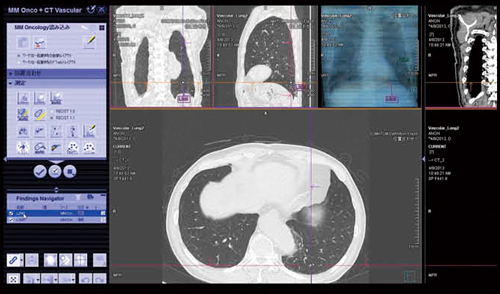

syngo.viaでは,血管系のソフトウェアであるCT Vascular Analysisと,肺野の結節影を自動検出する腫瘍系のソフトウェアのCT Lung CAREを,同じ症例に対して同時に適用した読影が可能である。

血管系のCT Vascular Analysisでは,三次元画像によるステントグラフト術後の評価などのほか,ターゲットとなる血管のcurved MPR像と短軸断面像などがあらかじめ選択された状態で表示され,内腔の評価や計測などが行える。また,腫瘍系のCT Lung CAREでは,肺野結節性病変の自動検出が可能で,なかでも,末梢の肺結節では,読影医でも気づきにくい2〜3mm程度の小さな結節や,肺血管に接している結節も検出できる。

読影フローとしてまず,CT Vascular Analysisによって血管系の評価を行っているが,頸動脈,腎動脈,ステントなどの血管がすでに選択された状態で画面が立ち上がり,それぞれの血管の様子がスムーズに確認できる(図3)。この症例では,run-offやステントの状態も良好に描出されている。ただ,詳細に見ると下腸間膜動脈を介するtypeⅡのエンドリークが認められた(図4)。同時に,肺野の評価は,MM OncologyのCT Lung Careで行ったが,こちらも画面を起動すると,すでに肺野の結節が自動的に拾い上げられており,肺野の転移性病変についても,短時間で読影が行える(図5)。

図5 syngo CT Vascular Analysisとsyngo CT Lung CAREによる肺結節の検出